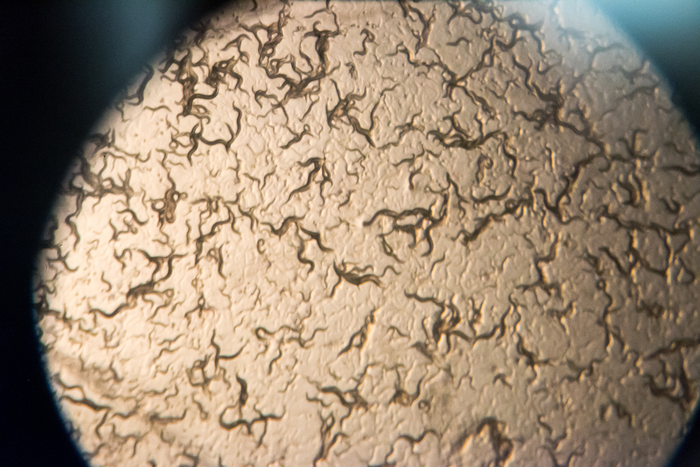

For this study, researchers altered genes of tiny roundworms known as C. elegans, mimicking the mutations found in patients. The worms share roughly half their genes with humans, and their basic features allow inexpensive and rapid experimentation for a range of neurological diseases. UA researchers can induce Parkinson’s-like effects in the worm’s dopamine neurons, as a proxy for testing the loss of neurons in the human brain as part of the disease.

Prior findings using the Caldwells’ worm models have repeatedly led to results later validated in human research, and the study discussed in the paper is another strong endorsement of the worm as a preclinical model for neurodegenerative disease research.